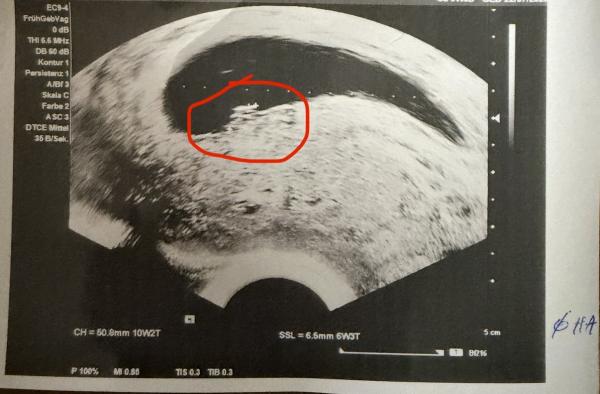

Heyy ihr, Ich hab eine Frage ob sowas in der Art hier auch schon jemand erlebt hat. Rechnerisch (letzte Menstruation 15.10.) müsste ich mich nun in etwa in der SSW 10 befinden. Letzte Woche und die Wochen davor beim Frauenarzt war auf dem Ultraschall außer der Fruchthöhle nichts zu sehen und es wurde schon immer von einem Windei gesprochen. Nun war ich heute wieder und plötzlich war auf dem Bild etwas zu sehen (siehe Bilder). Ich weiß es sieht nach nichts aus und wäre auch viel zu spät, aber gibt es sowas? Man sieht auch nicht viel auf dem Bild. Die FA meinte dann aber, dass jetzt doch iwas da ist, man sich aber nicht all zu viel Hoffnung machen solle..  hat jemand schon mal eine ähnliche Erfahrung gemacht? Ist iwie komisch für mich gerade.. LG und besinnliche Tage

Hallo guten Abend GruGru und frohe Weihnachten! Bist du dir sicher, dass die letzte Periode am 15.10. war? Hast du zufällig immer mal längere Zyklen < 30 Tage ?  Du weißt bestimmt mittlerweile, dass man spätestens ab 7+0 (8ssw) einen Embryo mit Herzaktivität sehen sollte.  Auf deinem US Bild (was echt ne gute Quali hat) kann man dort einen (angedeuteten) Dottersack erkennen, was darauf hinweisen könnte, dass da ein Embryo ist. In spätestens einer Woche sollte man einen sehen. Genau so ein Bild habe ich bei 6+0 gehabt (bei mir war die zeitliche Entstehung aber genau, da es ein Kryo Versuch war. Eine Woche später Embryo + Herzschlag). Ich bin nämlich laut Periode 14 Tage im Voraus wie bei dir (1.10.) und deshalb dürfte das eigtl zeitlich alles nicht so passen bei dir... :-(  Hoffnung würde ich trotzdem noch nicht aufgeben. Die Ärztin hat Recht. Eventuell gibt's ja irgendwoooo ein Rechenfehler?? Fühl dich lieb gedrückt!